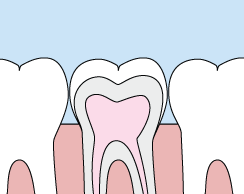

crownsCrowns are a cosmetic restoration used to improve your tooth’s shape or to strengthen a tooth. Crowns are most often used for teeth that are broken, worn, or have portions destroyed by tooth decay.

A crown is a "cap" cemented onto an existing tooth that fully covers the portion of your tooth above the gum line. In effect, the crown becomes your tooth’s new outer surface. Crowns can be made of porcelain, metal, or both. Porcelain crowns are most often preferred because they mimic the translucency of natural teeth and are very strong.

Crowns or onlays (partial crowns) are needed when there is insufficient tooth strength remaining to hold a filling. Unlike fillings, which apply the restorative material directly into your mouth, a crown is fabricated away from your mouth. Your crown is created in a lab from your unique tooth impression, which allows a dental laboratory technician to examine all aspects of your bite and jaw movements. Your crown is then sculpted just for you so that your bite and jaw movements function normally once the crown is placed.